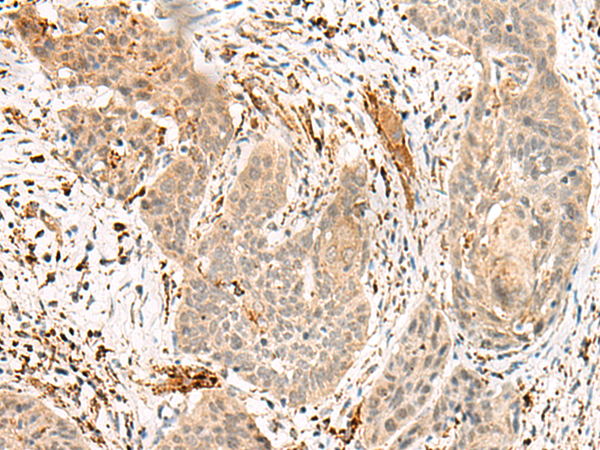

分类: 科研抗体货号: P07186别名: P21; CIP1; SDI1; WAF1; CAP20; CDKN1; MDA-6; p21CIP1应用: WB,IHC反应种属: Human